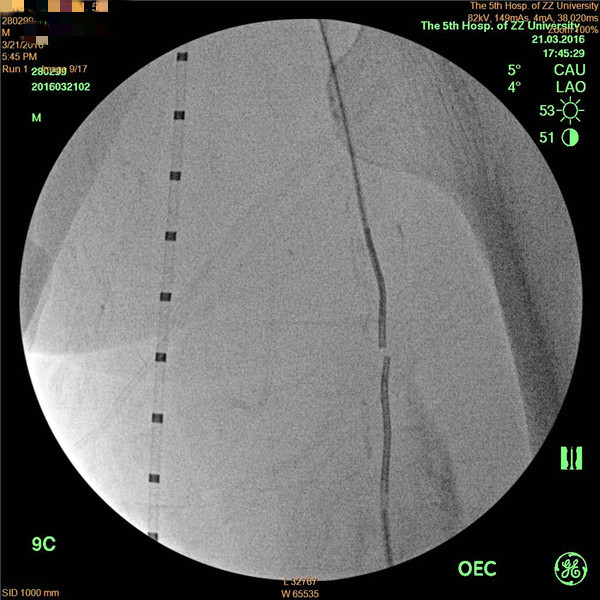

患者周先生,59岁,1年前无明显原因出现双侧小腿及足部发凉,活动后左足疼痛,3月前疼痛加重,出现左足第4及第5足趾发紫,并逐渐进展为足趾发黑、坏死,多处求医用药治疗,效果差,2周前左足疼痛进一步加重,并累及左足第3足趾发黑坏死,无法行走,严重影响了病人的生活质量(见图1)。慕名前来我院血管外科就诊。我院血管外科专家王兵教授为患者制定了详细的诊疗方案,下肢动脉CTA提示患者左侧股浅动脉多发粥样硬化斑块形成,管腔长段闭塞(见图2),明确诊断为“复杂下肢动脉硬化闭塞症”,积极术前准备后,王兵教授带领血管外科崔文军副主任、安乾主治医师、李攀峰医师给患者进行血管腔内介入治疗。术中DSA造影提示:股浅动脉长段闭塞,腘动脉通畅(见图3、图4)。单弯导管配合超滑导丝及微导丝,反复多次尝试顺行开通股浅动脉闭塞段均宣告失败,王兵教授决定采用逆穿技术,在DSA下穿刺腘动脉,成功后逆行置入单弯导管及超滑导丝,顺利开通股浅动脉闭塞段,逆行超滑导丝选入顺行单弯导管内,完成对接(见图5、图6),逆行导丝引出体外,引入球囊扩张股浅动脉闭塞段,股浅动脉闭塞段置入两枚金属裸支架后造影显示左下肢动脉全程通畅(图7、图8)。术后患者胫后动脉搏动恢复,静息性疼痛消失。 复查下肢动脉CTA:左下肢动脉血流通畅(图9)。

图3

图4